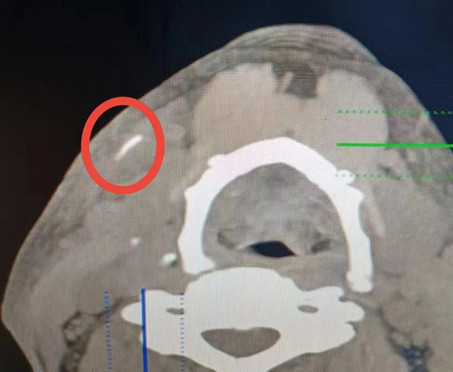

五官科主任李濤接診了此患者,專(zhuān)科檢查在右側(cè)頜下觸及大小約1.5cm*1.0cm腫塊,CT示右側(cè)頜下局部軟組織增厚伴高密度影,異物可能性大。后詳細(xì)與患者溝通獲悉一月余前曾吞咽過(guò)魚(yú)刺,高度懷疑是魚(yú)刺已游走至頜下并導(dǎo)致周?chē)M織感染及膿腫形成。遲則生變,李濤主任建議患者立即進(jìn)行手術(shù)治療,以免發(fā)性危及生命的嚴(yán)重并發(fā)癥。